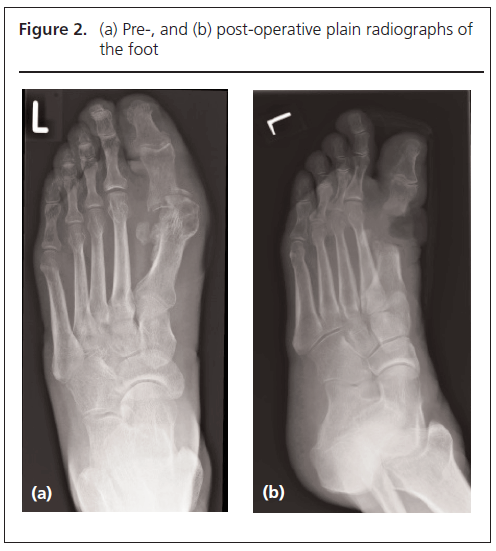

All wounds were reviewed at 48 hours by a podiatrist and a baseline postoperative radiograph was taken (Figure 2). Temporary footwear was provided to prevent flexion of the foot and to offload the operative site. If the bone culture was positive, further antibiotics were continued for 2 weeks or longer (depending on wound healing, soft tissue infection with advice from a microbiologist and also on progression of any infection on radiographs). Patients were followed up by the multidisciplinary diabetic foot team and community podiatry team until complete wound healing (Figure 1d) and resolution of osteomyelitis on serial radiographs. Bespoke footwear was provided via the orthotics department after wound healing.

318 Saeed Figure 2